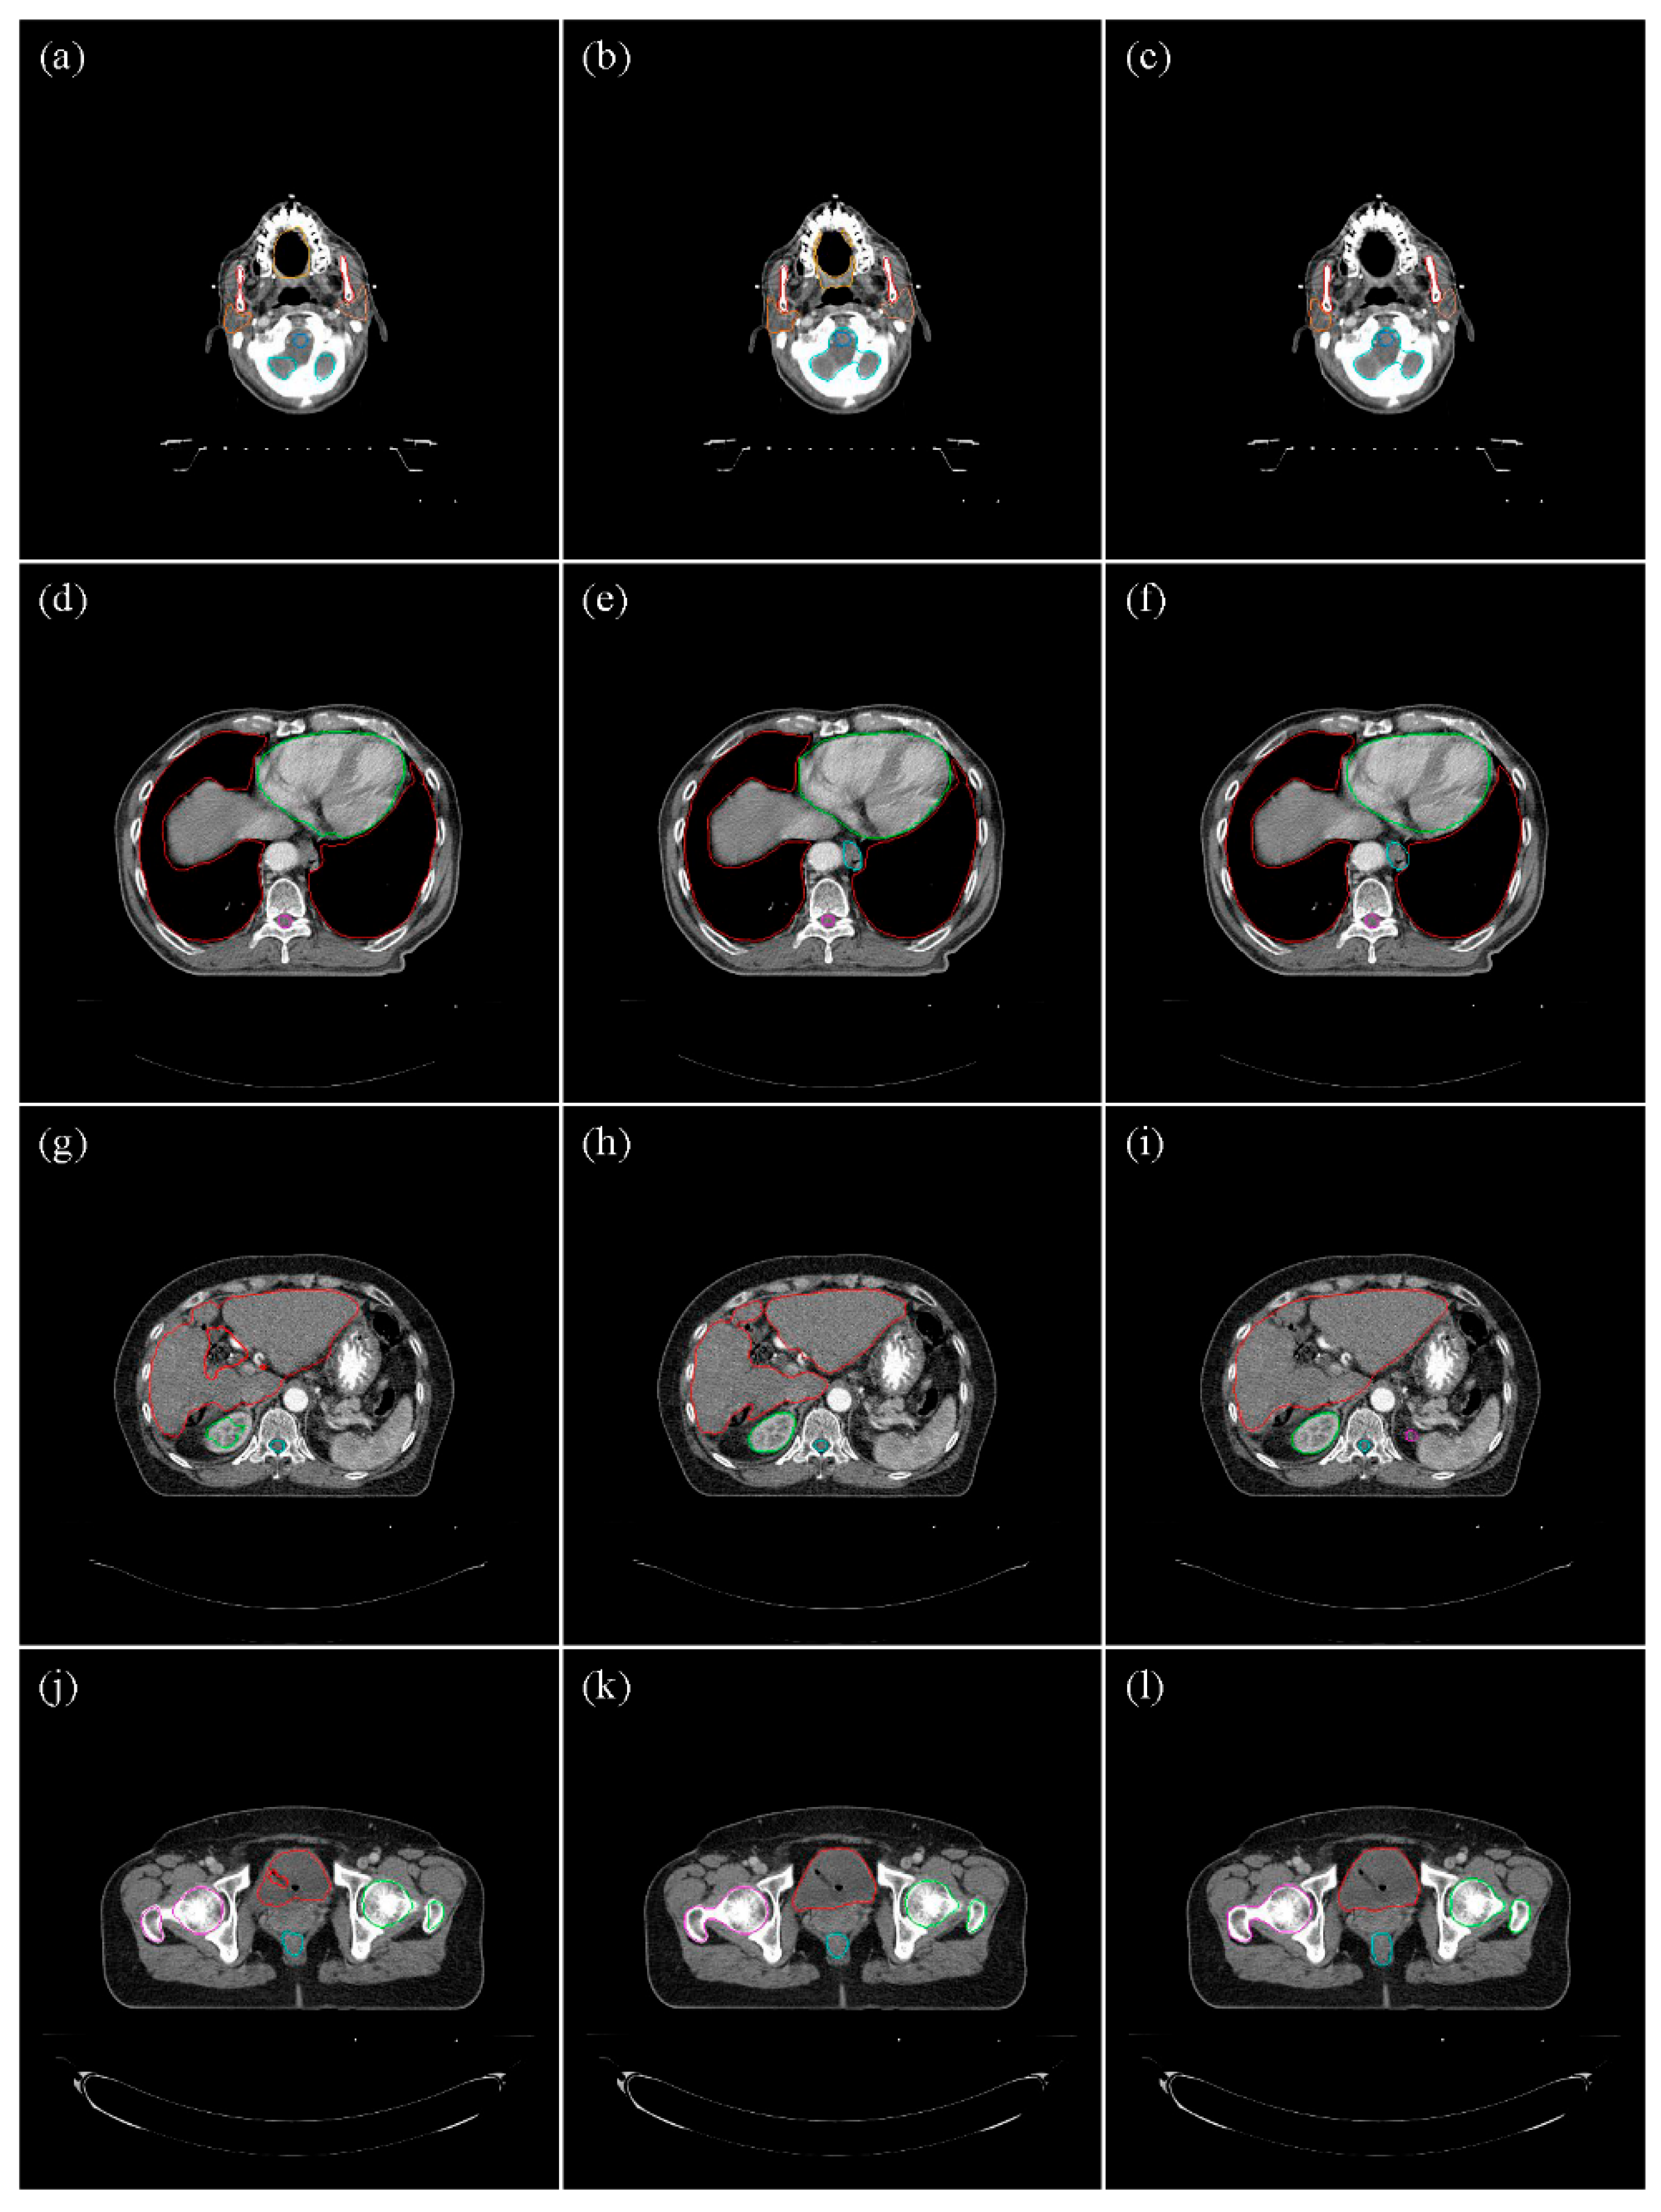

3.1. Head and Neck Organs

3.2. Thoracic Organs

3.3. Abdominal Organs

3.4. Pelvic Organs